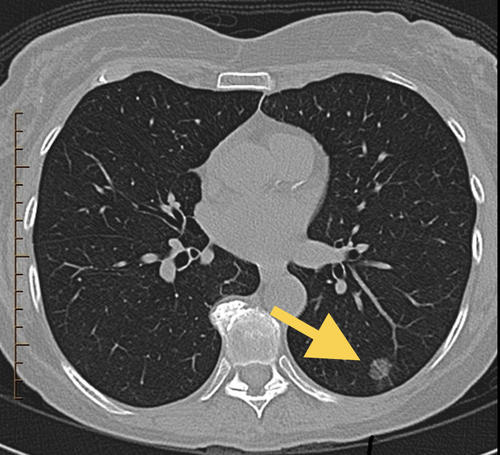

患者陈女士近日在单位体检中查胸部平扫CT时发现左侧肺部有一个直径约10mm的肺部纯磨玻璃样结节(如图,磨玻璃结节指:密度较低,在CT图像上像一块磨玻璃似的病灶)。

经过MDT团队中包括胸心外科、呼吸科、影像科、病理科等多门学科专家合作诊疗后,各位专家认为陈女士左肺的磨玻璃病灶直径较大,且病灶旁可见短小毛刺,病灶内部密度稍有不均,考虑早期肺癌可能性大,建议限期行手术切除,明确病理结果的同时进行外科手术治疗。

后陈女士在我院胸心外科接受了胸腔镜手术,术后的病理结果为:原位腺癌伴微浸润。属于早期肺癌,治愈率接近100%,预后极好。因陈女士及时对肺部病灶进行处理,目前尚未达到浸润性腺癌,无需行扩大手术治疗,术后也无需使用化疗或其他辅助治疗。